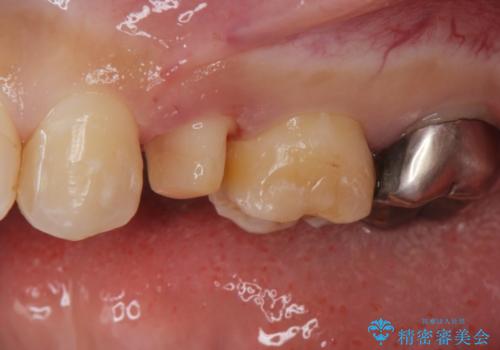

- 他院で被せた保険の白い被せ物(樹脂)をセラミックの被せ物に変えたいとの事で来院。

被せ物を外し、虫歯がないことを確認してセラミックの被せ物(ジルコニアクラウン)の治療を行いました。

白くて適合の良い被せ物が入りました。

セラミックは劣化することがなく虫歯の再発のリスクが低くなります。